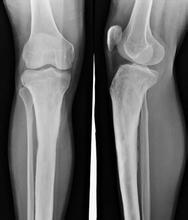

• [分型] 膝关节退行性骨关节炎

导读: 膝关节退行性关节炎又称膝关节肥大性关节炎,多见于老年人,因而也称作老年性关节炎。